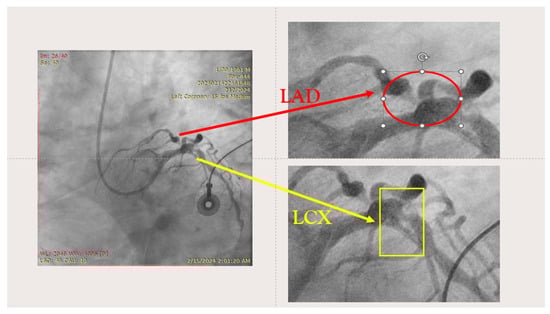

- Engage the left coronary artery with an EBU 4.0/8F guiding catheter. Wiring the three branches of the trifurcation (Floppy guide wires in LAD and RI, Hydrophilic guide wire in LCX) (Figure 14).